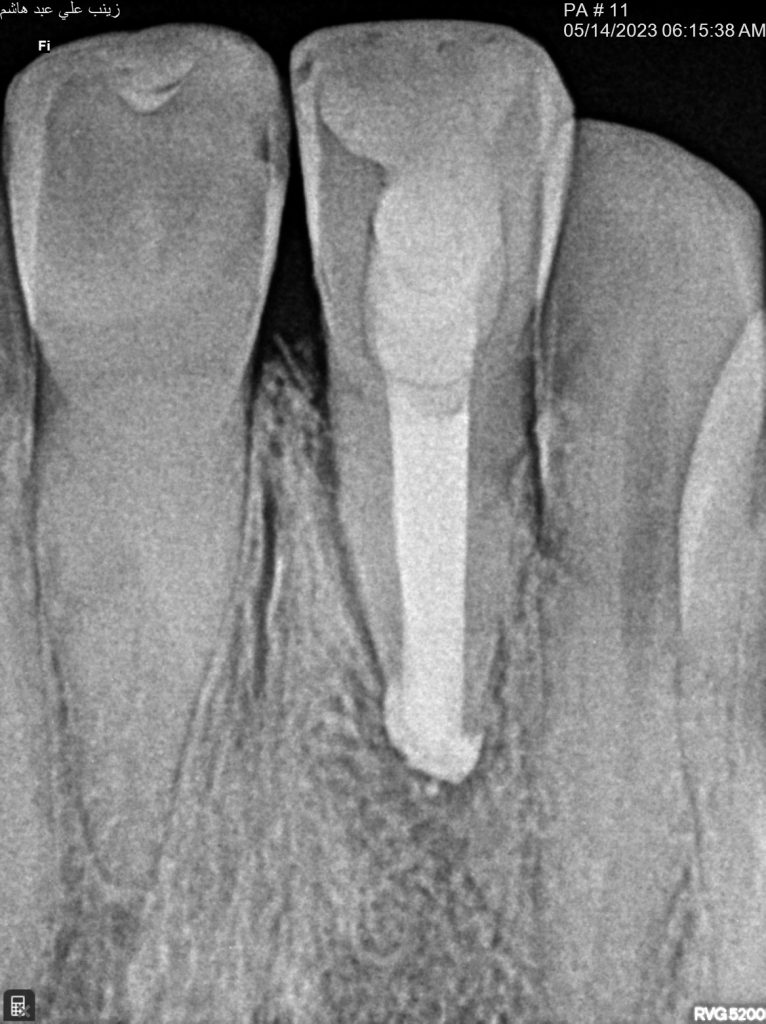

finally filled the canal with bio ceramic putty

Collagen sponge and obturation

Two years follow up